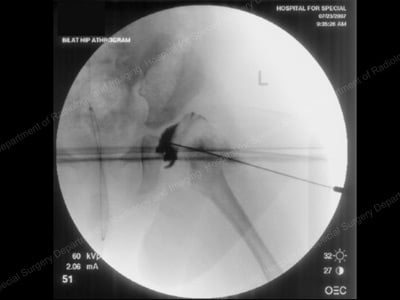

Arthrogram image of dislocated hip in the operating room.